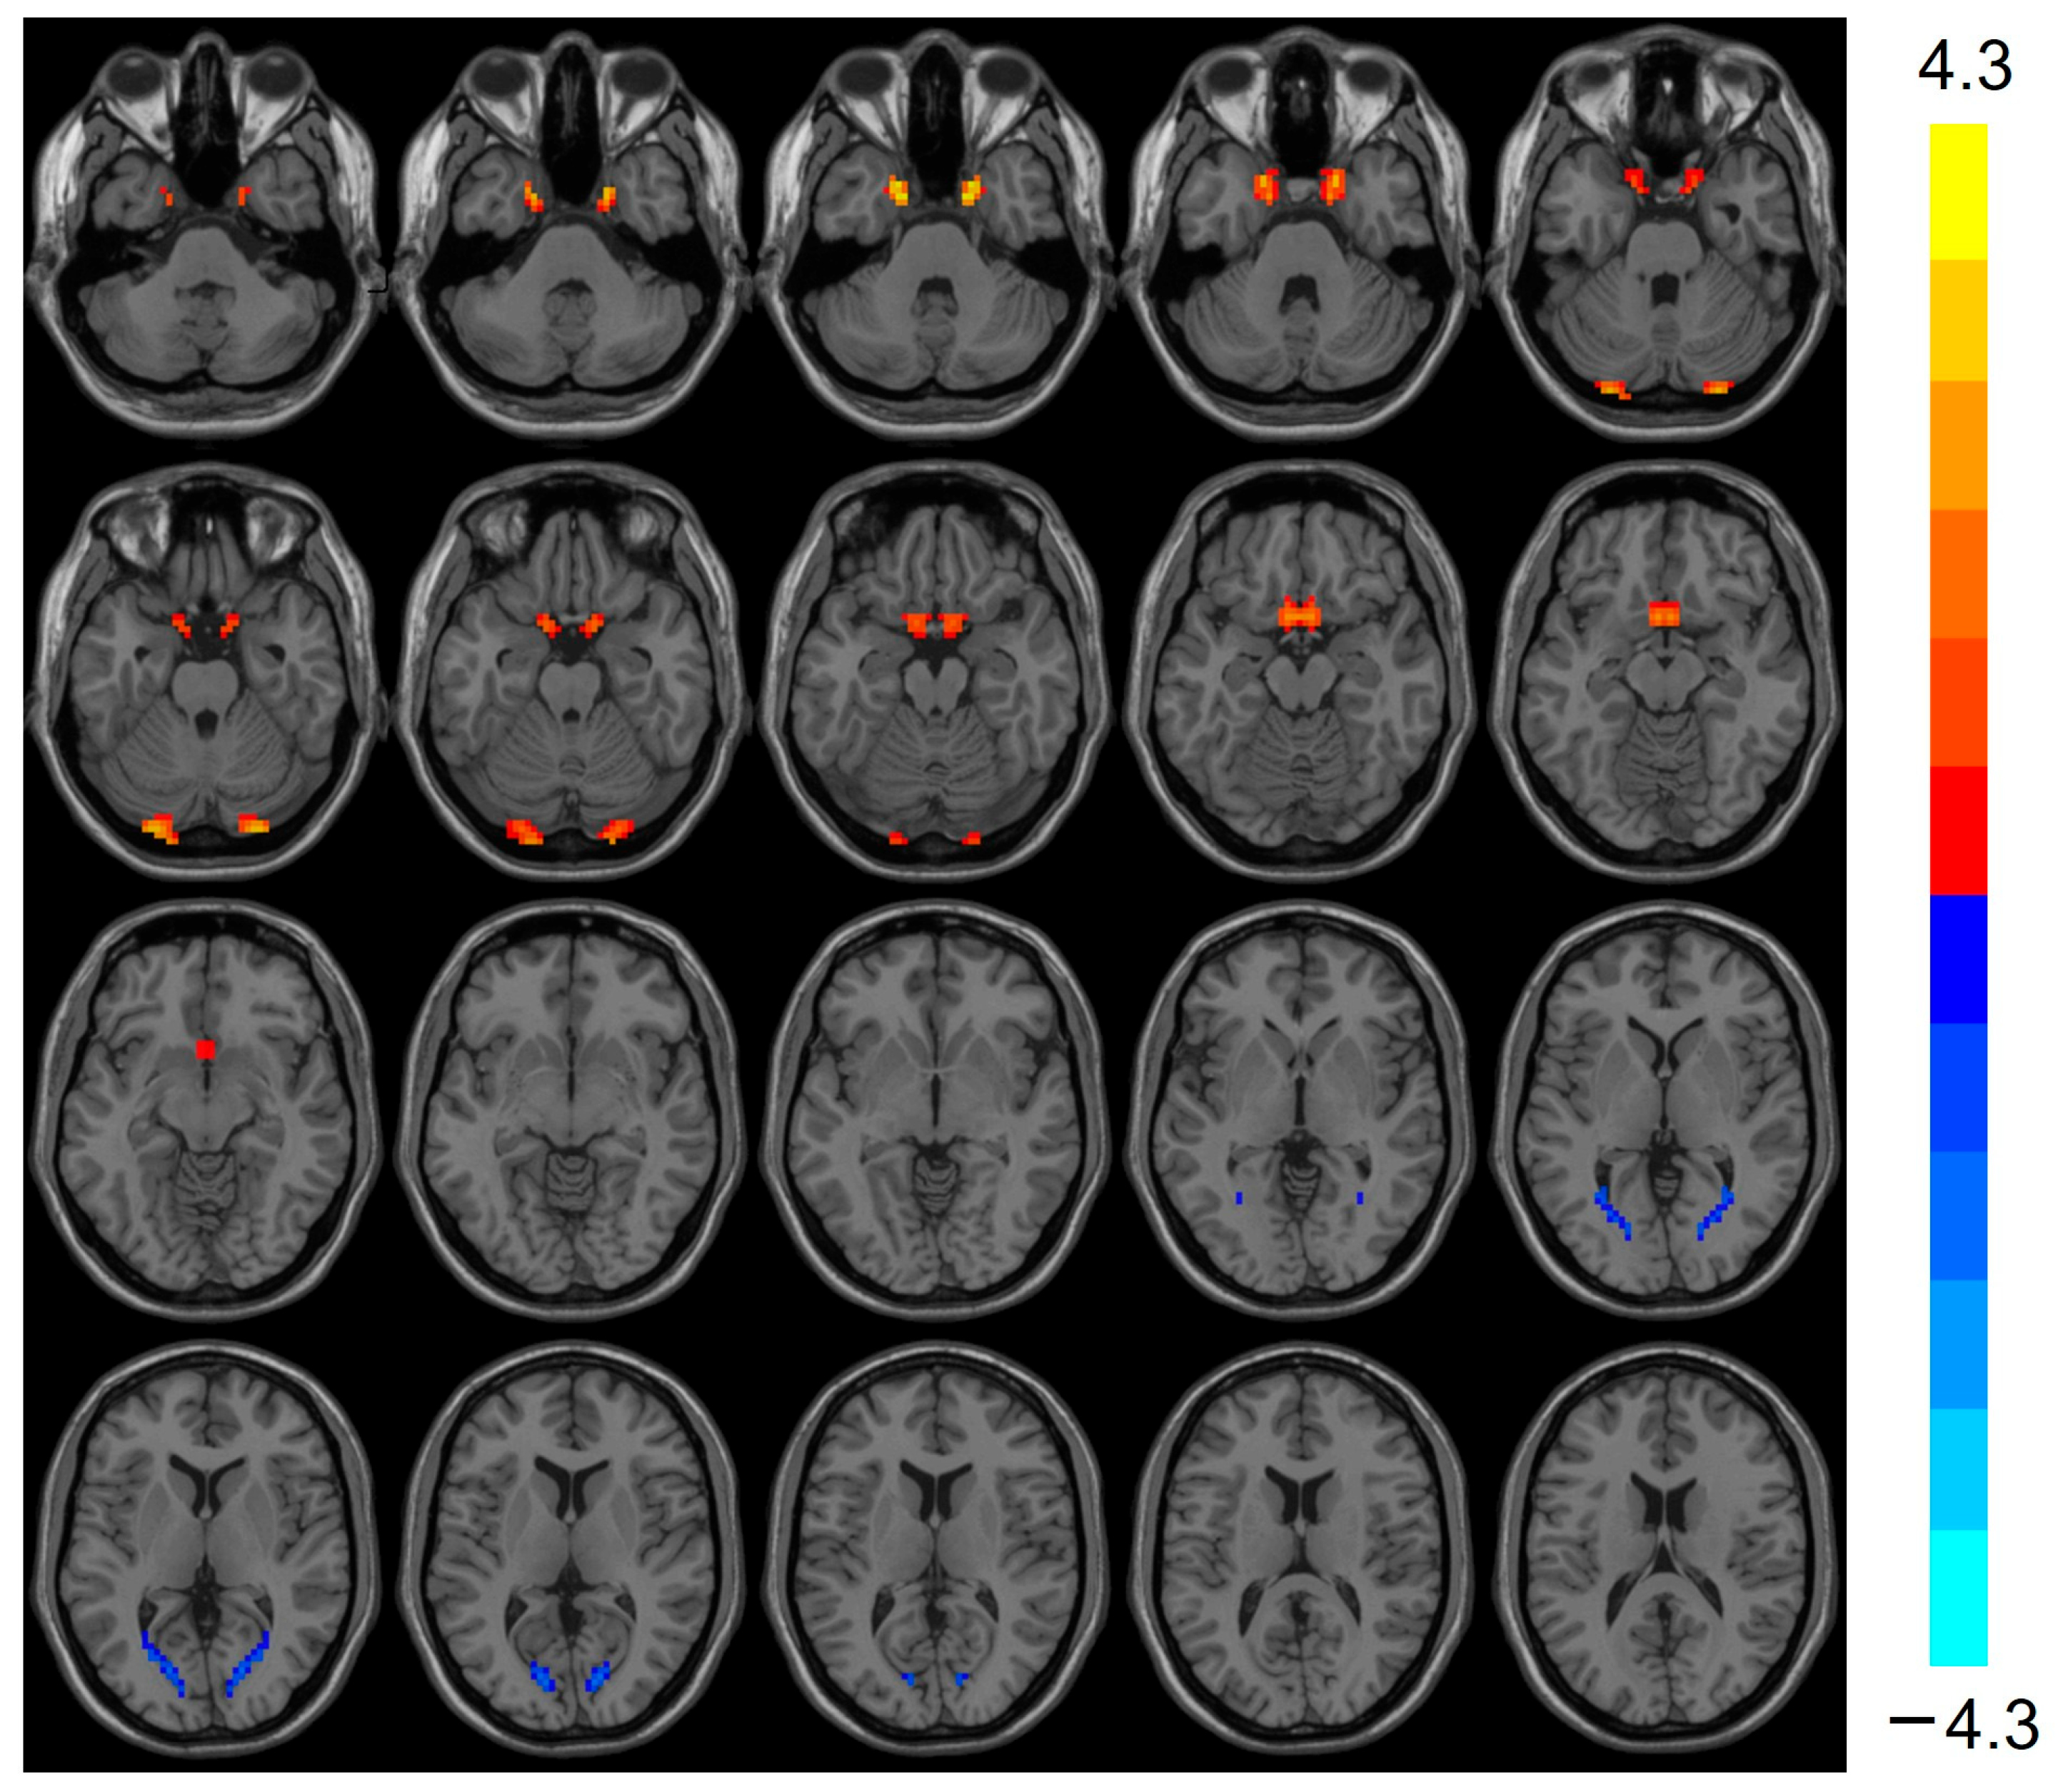

Compared with the control group, the heart transplantation group exhibited reduced ReHo in the Frontal_Sup_R (t = −4.422, p < 0.001), Thalamus_L (t = −3.911, p < 0.001), and Calcarine_L (t = −3.640, p < 0.001), while the ReHo of Temporal_Sup_L was elevated (t = 4.609, p < 0.001) (see Table 2 and Figure 1).

Figure 1.

Images show decreased ReHo for Frontal_Sup_R, Thalamus_L, and Calcarine_L in the heart transplantation group (blue) and increased ReHo for Temporal_Sup_L (red). Color bars on the right show t-values. ReHo, regional homogeneity.

ReHo, calculated using Kendall’s concordance coefficient (KCC) to assess the consistency of adjacent voxels in the time series of rs-fMRI, indirectly reflects the synchronization of local spontaneous brain activities [20]. Previous studies have shown that patients with cognitive impairment exhibit altered spontaneous brain activity in the resting state. Zhang et al. found that ReHo in the medial prefrontal cortex and precuneus was significantly lower in patients with cognitive impairment compared to healthy subjects [21]. Liu et al. noted that ReHo in the right superior temporal gyrus and right middle temporal gyrus of patients with mild cognitive impairment (MCI) was significantly lower than that of healthy subjects [22]. In the present study, reduced ReHo in the Frontal_Sup_R, Thalamus_L, and Calcarine_L suggests disrupted local functional integration in these regions. The superior frontal gyrus is a crucial component of the prefrontal lobe, which is responsible for integrating internal and external environmental information, extracting environmental memories, and playing a central role in attention and executive function, and its decreased ReHo may directly contribute to the observed deficits in attention and abstraction tasks [23]. The thalamus acts as an information relay station for the brain and plays a key role in processing and transmitting sensory information [24]. It is also recognized as a critical node for coordinating cognitive functions. Its reduced ReHo could impair information transfer between cortical and subcortical regions, exacerbating memory and language deficits [25]. The calcarine sulcus belongs to the occipital cortex, which is involved in memory, speech, attention, and executive functions in addition to visual information processing as an important visual center [26]. This finding is generally consistent with our results, which showed that VMHC in heart transplant patients is significantly correlated with cognitive function. The resting-state brain activity in the occipital lobe is involved in the entire cognitive process beyond visuospatial structures. Conversely, we also found elevated ReHo in the Temporal_Sup_L in heart transplant patients. The superior temporal gyrus, which is part of the temporal lobe, contains the hippocampus and parahippocampal gyrus, which are associated with memory. The superior temporal gyrus also contains areas 41 and 42 and the transverse temporal gyrus, which form the auditory cortical area and are thought to be involved in cognitive processes and language function. Elevated ReHo in the superior temporal gyrus may reflect compensatory neural recruitment to mitigate language-related cognitive decline [27].